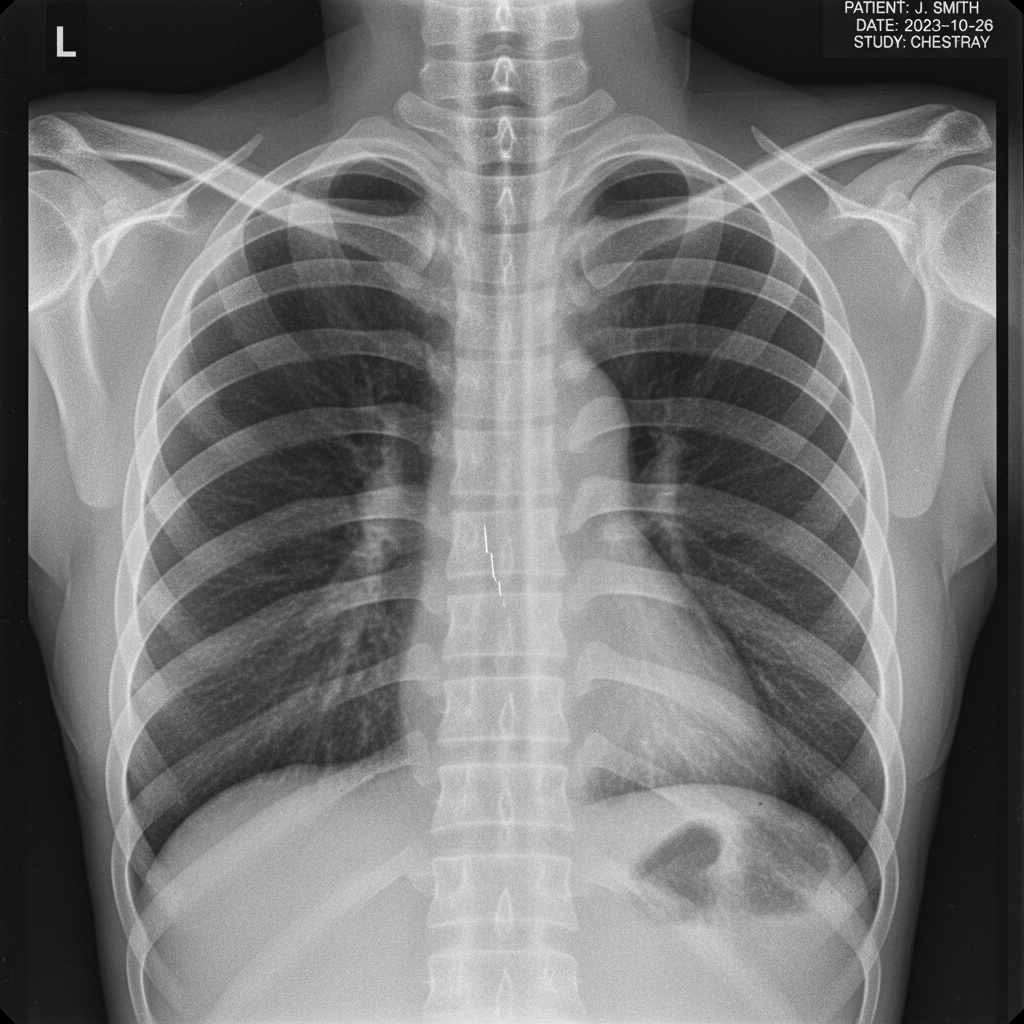

가장 먼저 할 일은 정형외과나 흉부외과에 방문하여 정확한 진단을 받는 것입니다. X-ray나 CT 촬영을 통해 골절 여부와 정도를 확인해야 해요. 의사 선생님의 지시에 따라 진통제를 처방받고, 필요한 경우 복대나 테이핑으로 고정을 하는 것이 좋습니다.